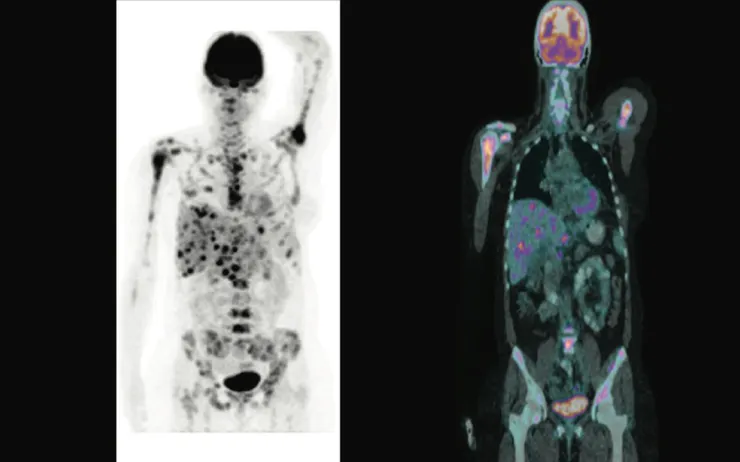

上圖中的黑色部分就是有 FDG 的位置,除了大腦和膀胱等器官本來就會聚集葡萄糖以外,這位病患的肝和許多骨頭內都有惡性腫瘤,癌細胞擴散的情況一目瞭然(患者大概也沒多少時日了⋯⋯)。除了左圖黑色和右圖彩色的部分是 PET 的成像以外,影像背後的其他人體構造是結合 CT(電腦斷層)做出來的,關於這個技術先暫時不談。